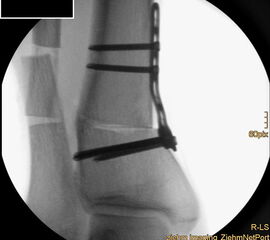

Auch hier wird die Korrektur im CORA (Center oft Rotation and Angulation) durchgeführt. Primär werden intraoperativ unter Bildwandler Kontrolle Kirschner Drähte als Sägelehre konvergierend eingebracht. Dann wird der geplante medialbasige Keil mit der oszillierenden Säge entfernt. Die laterale Kortikalis sollte geschont werden, sie dient als Drehpunkt für die Osteotomie. Die Osteosynthese kann dann im Sinne einer Zuggurtung ein besonders stabiles Konstrukt bilden. Liegen mehrdimensionale Deformitäten vor, die eine Korrektur in Translations- und Rotationsebene erfordern, ist eine Durchtrennung der lateralen Kortikalis notwendig, ebenso bei ausgedehnten Korrekturen mit Keilhöhen über 10mm 218.

Wir benutzen zur Osteosynthese 3,5 mm LCP T-Platten. In der intraoperativen Röntgenkontrolle kann im seitlichen Bild die Zentrierung des Talus überprüft werden, und ggf. durch eine milde extendierende oder flektierende Korrekturkomponente verbessert werden 18. Eine begleitende Deformität der Fibula korrigieren wir üblicherweise mit einer z-förmigen Osteotomie die wir mit einem 1/3 Rohrplättchen sowie einer Zugschraube sichern 18.